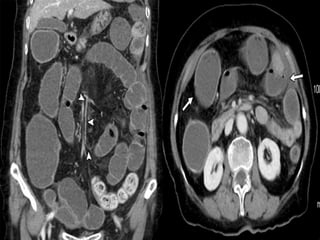

CT Scan Findings In Mesenteric

Ischemia

Specific CT signs

 Thromboembolism in the mesenteric

vessels

 Lack of bowel enhancement

 Circumferential bowel wall thickening:

-Target sign

 Intramural gas

 Portal vein gas

 Focal / diffuse bowel dilatation

 Bowel obstruction

 Increased attenuation of mesenteric fat (edema)

 Vascular engorgement

 Variable enhancement pattern

 Ascites

SMV THROMBOSIS

ARTERIAL OCLUSIVE ISCHEMIA VENOUS OCLUSIVE ISCHEMIA

SMA THROMBOSIS SMV THROMBOSIS

NO /SUBTLE BOWEL ENHANCEMENT HYPO/HYPERDENSE BOWEL WALL

THINNED BOWEL WALL (PAPER THIN

BOWEL )

SIGNIFICANT BOWEL WALL

THICKENING

NO MUCOSAL ENHANCEMENT MUCOSAL ENHANCEMENT

BOWEL LOOP DILATATION ONLY AFTER

INFARCTION

DILATED BOWEL LOOPS WITHOUT

LATE STAGES –MESENTERIC FAT

STRANDING,EDEMA/HEMORRHAGES

MARKED FAT STRANDING AND

HEMORRHAGE